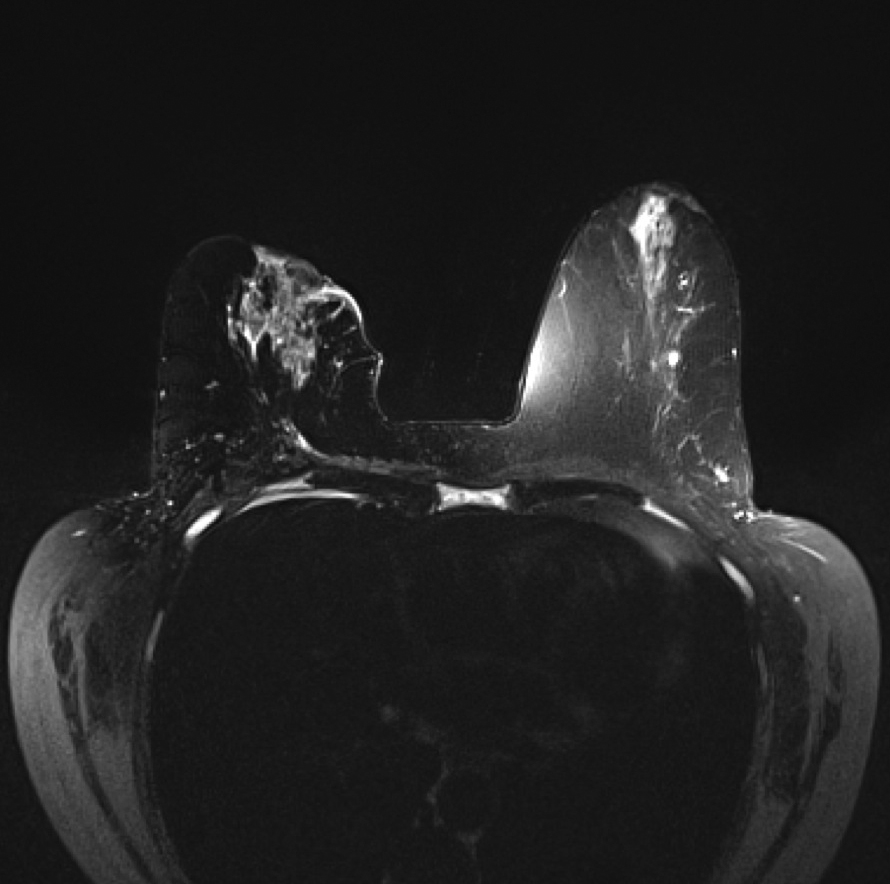

Magnetic resonance imaging (MRI) of the breast revealed a large right retroareolar mass with skin and nipple retraction and right axillary lymphadenopathy highly suspicious for metastatic breast cancer.

Figure 6. MRI T2 of the breasts shows a large right retroareolar mass with skin and nipple retraction. (click on picture for higher resolution image)

Figure 6.? MRI T2 of the breasts shows a large right retroareolar mass with skin and nipple retraction.